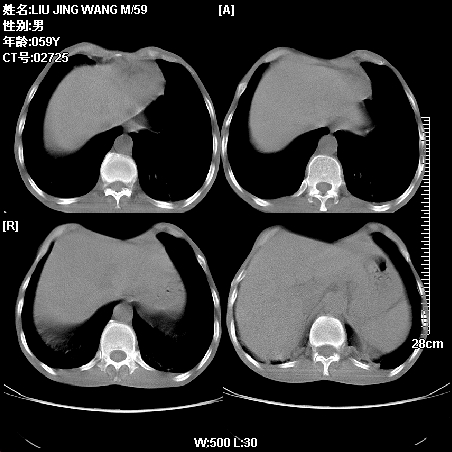

肿瘤科住院病人,都有食管癌史,都有放化疗治疗,两下肺病变是转移灶?还是其他原因造成?请老师指点

病例一 现呼吸困难,经抢救多次,咳嗽咳痰,发现食管癌2个多月

符合放射性肺炎,第一例不除外坠积效应